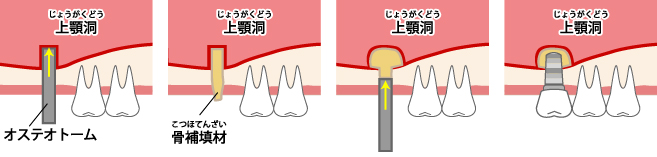

ソケットリフト

ソケットリフトは、残っている骨の量が5mm以上ある場合に適用される骨造成術です。上顎洞と呼ばれる目の下・鼻の横の空洞部分に隙間を作り、そこに骨補填剤を注入します。サイナスリフトより簡易な骨造成術です。